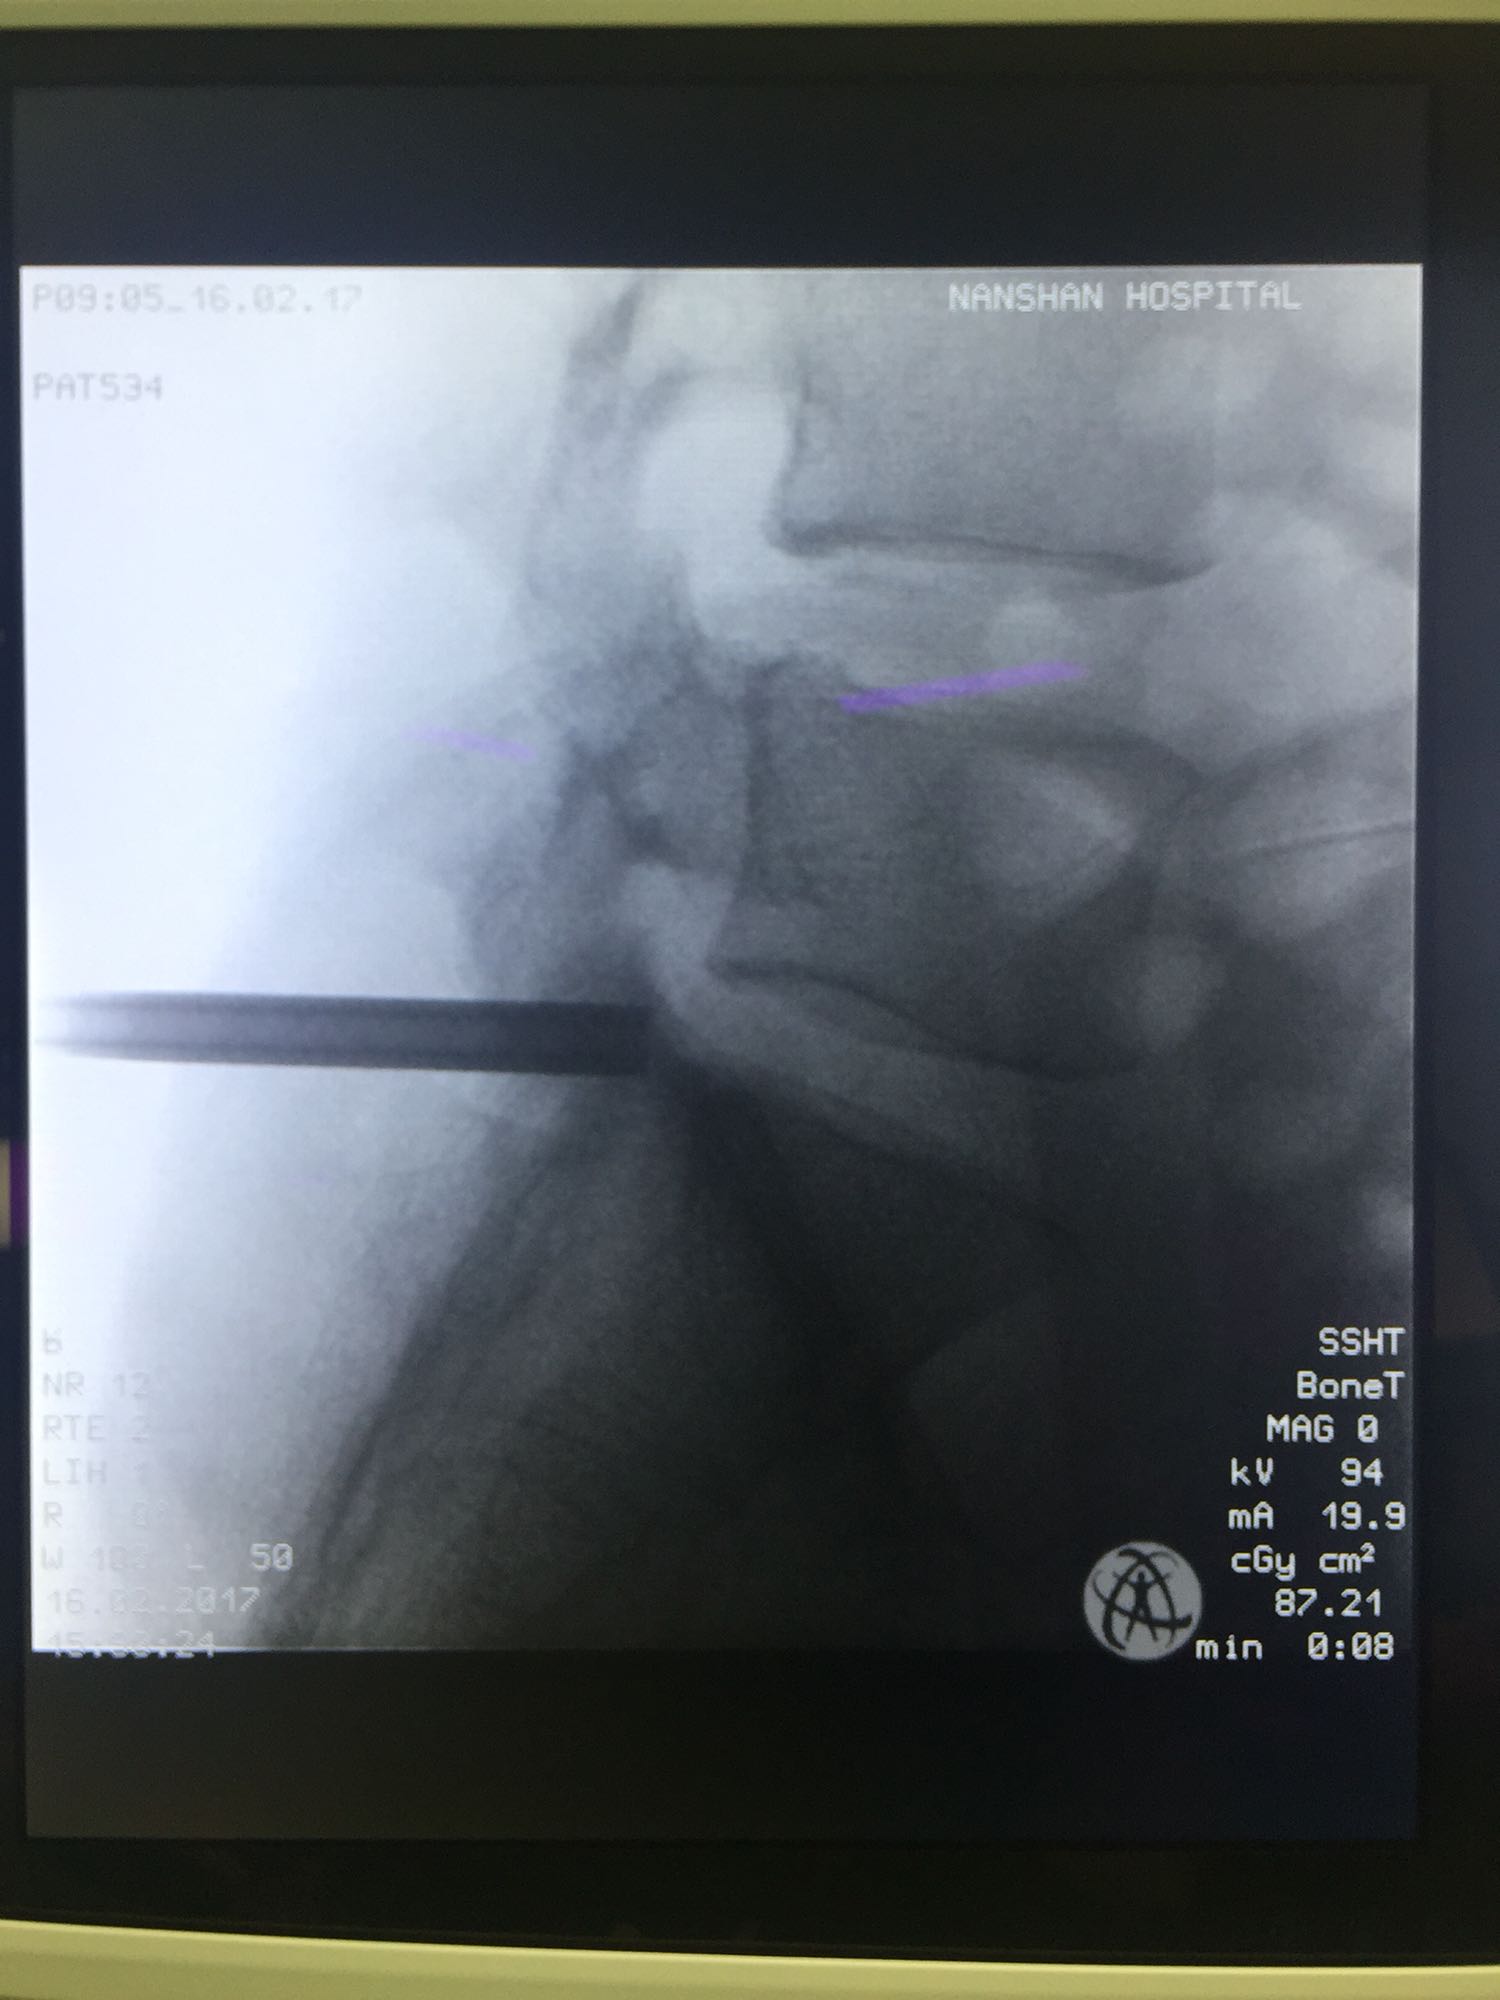

椎间孔镜下腰5骶1椎板间隙入路髓核摘除术

诊断:腰5骶1椎间盘突出症 治疗方案:椎间孔镜下经椎板间入路髓核摘除术